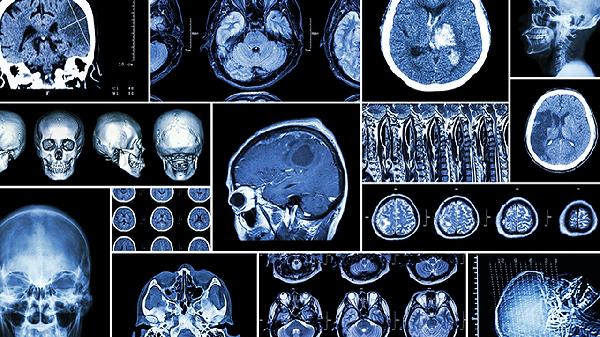

颅骨修补的较佳时间是何时

颅骨修补的较佳时间通常在颅骨缺损后3-6个月,具体需结合患者伤口愈合情况、全身状态及原发病控制程度综合评估。